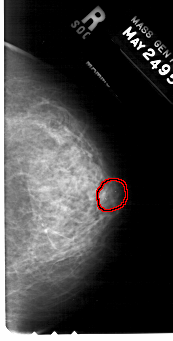

FILE: A_1320_1.RIGHT_CC.OVERLAY

TOTAL_ABNORMALITIES 1

ABNORMALITY 1

LESION_TYPE CALCIFICATION TYPE AMORPHOUS DISTRIBUTION CLUSTERED

ASSESSMENT 4

SUBTLETY 3

PATHOLOGY BENIGN

TOTAL_OUTLINES 1

BOUNDARY